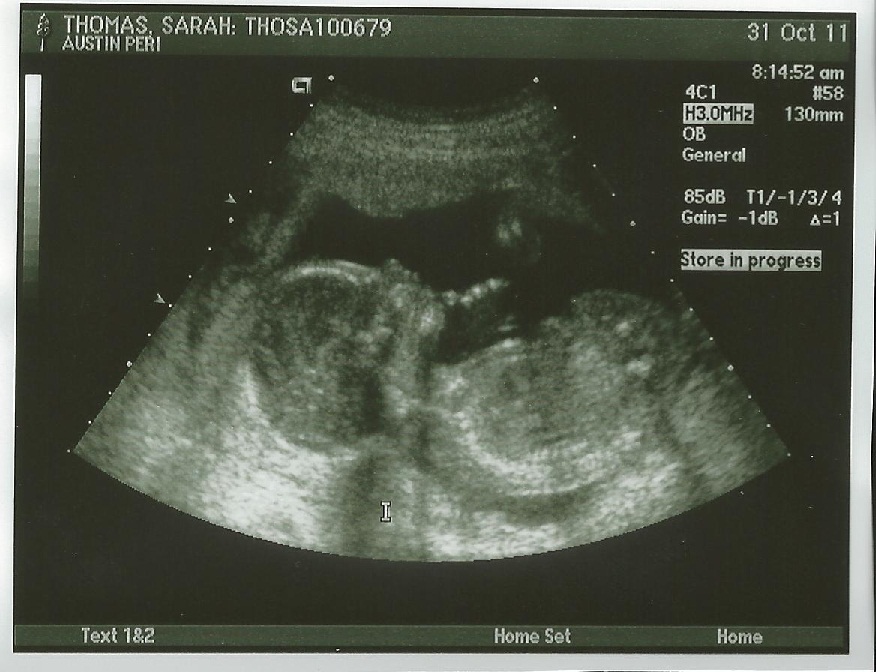

We had our 20 week ultrasound this week, and our baby girl passed with flying colors. Knowing her Type A, first born-parents, we're not really surprised:) It's actually pretty incredible what they can test for at this ultrasound, literally measuring almost every body part and major organ. While I haven't been able to feel movement yet, she is extremely active when we see her on screen (the ultrasound tech even used the word "sassy"... yikes).

Baby T's profile with her hand under her chin. Although we're pretty biased, we think she's just beautiful;)